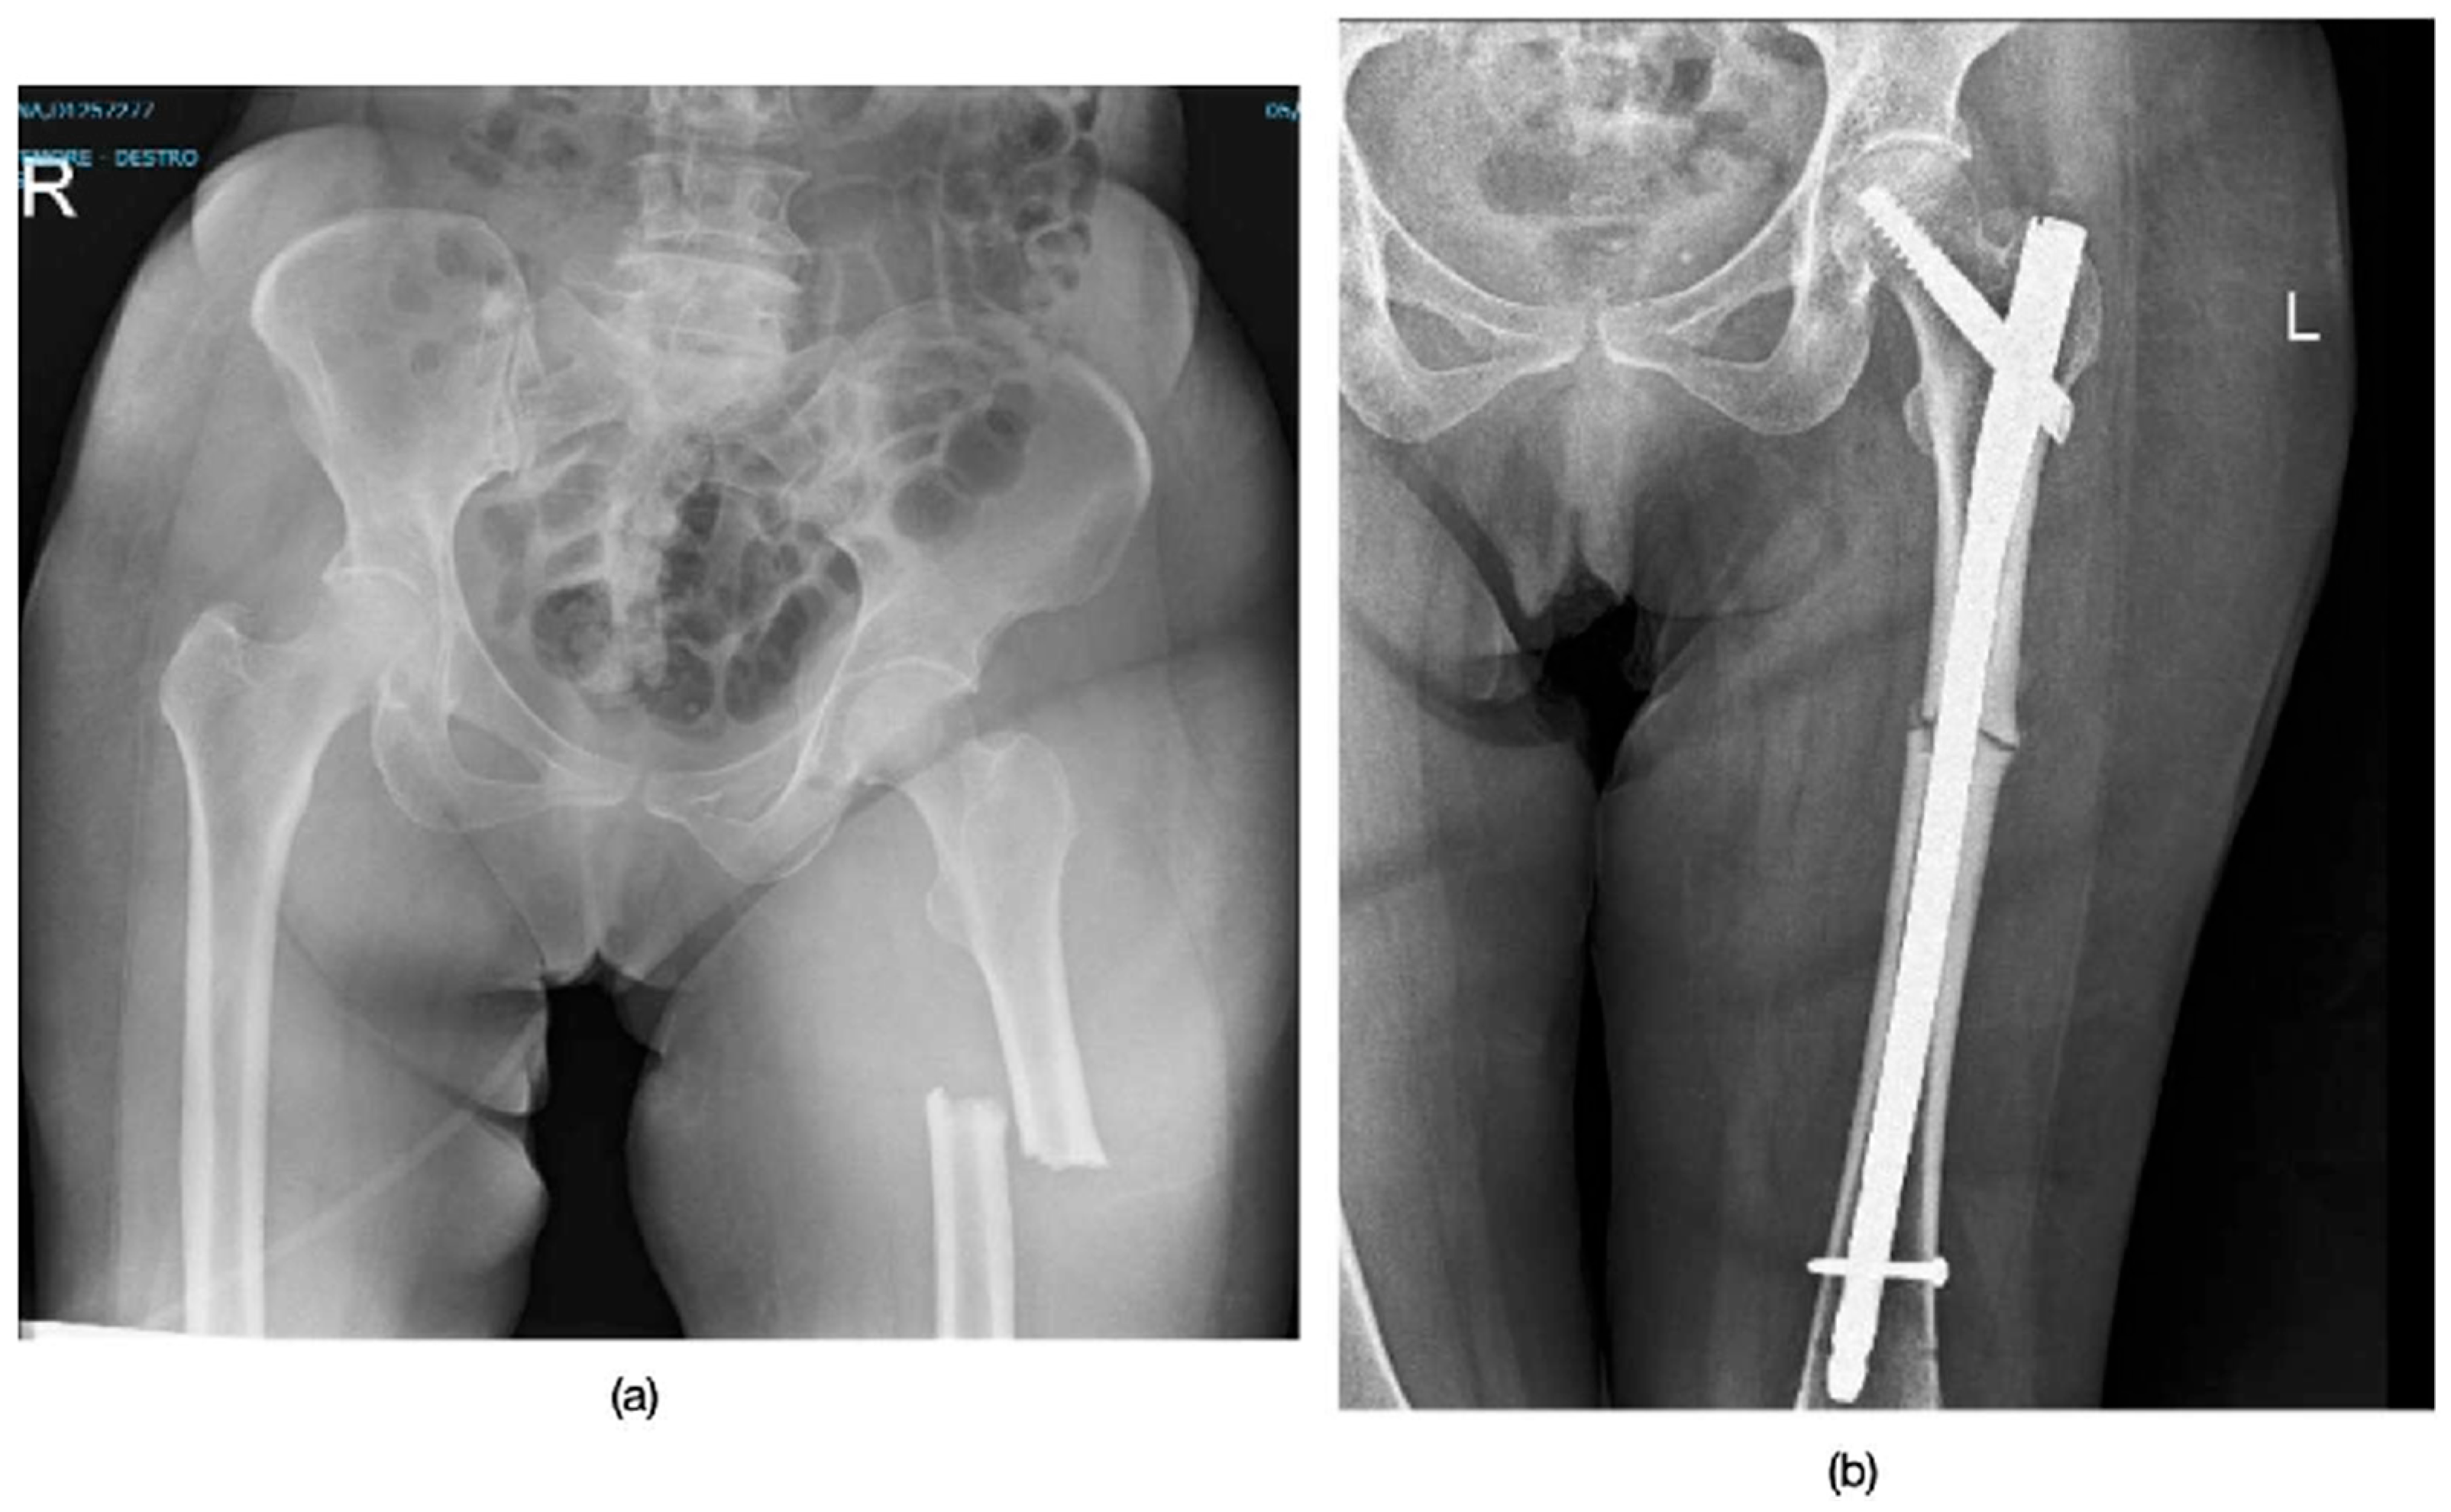

2.3. Surgical Treatment

3.2. Treatment and Healing Process

| Mean Age | Involved Side | Localization | Time of Use of Bisphosphonates | Surgical Treatment | Pseudoarthrosis |

|---|---|---|---|---|---|

| 70.3 ± 6.5 y | 4 Right, 2 Left | 2 subtrochanteric 4 mid-diaphyseal | 7.3 ± 1.5 y | long intramedullary nail | 0% |

| Radiographic Healing Time | Quality of Life | ROM Average Recovery Time | Residual Pain at 12 Months |

|---|---|---|---|

| 5 ± 1.5 months | SF36 of 77 ± 15.4 pre (before surgery) SF36 of 57 ± 12.5 post (a year after surgery) | 4.5 ± 1.2 months | VAS of 2 ± 1 |